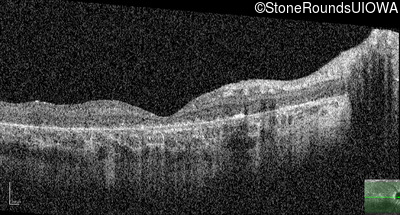

AR Stargardt Disease (IIA)

Age at visit: 8 years

This 8 year old girl had normal vision until age 6 when she failed a school vision screening. That year, she was able to play softball well, but this year she often loses sight of the ball and is often hit by it.

Diagnosis & molecular findings

Disease Gene Allele 1 variant(s) Allele 2 variant(s) Inheritance mode

AR Stargardt Disease ABCA4 IVS38-10T>C IVS38-10T>C AR